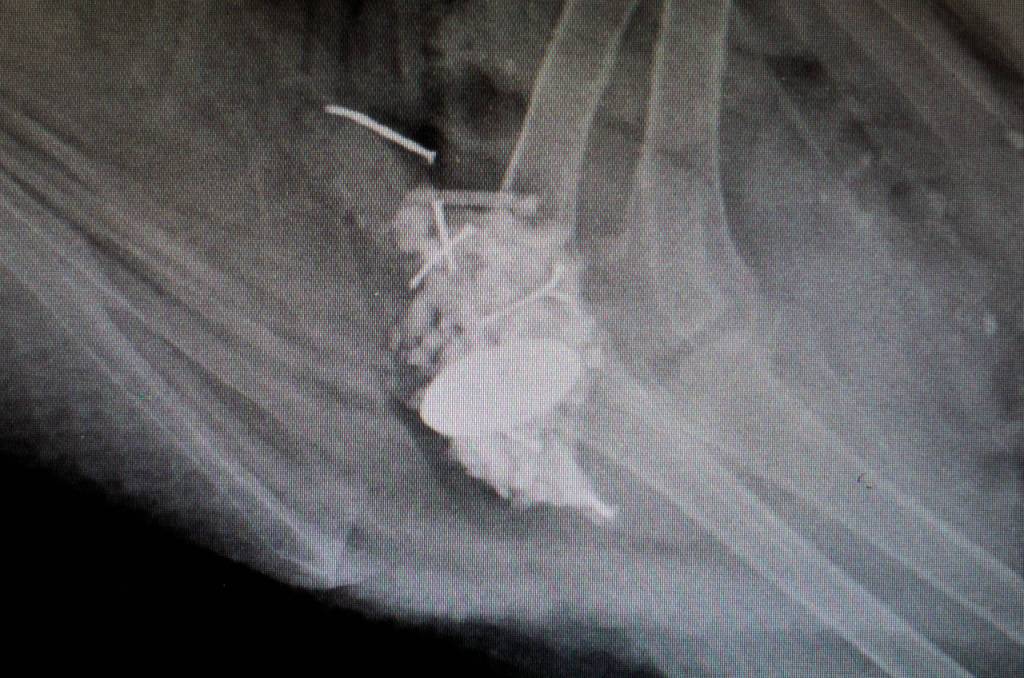

If needed, specialists such as a cardiologist or oncologist can be called in, but the center’s veterinarians do a variety of procedures on their own, such as blood tests and X-rays, echocardiograms and endoscopies, the latter of which involves using a camera to look inside a creature’s body. It’s different than in humans, Strunk said.